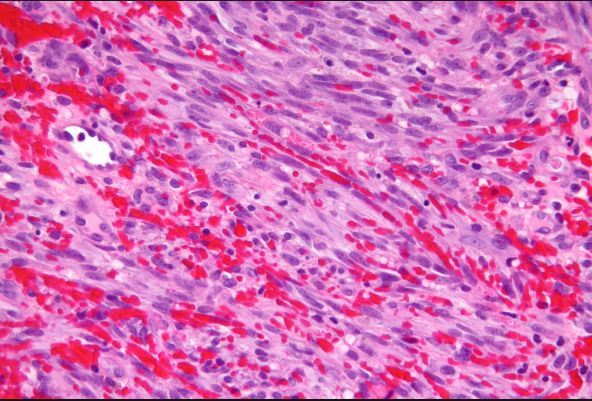

12

Q

What is this?

A

Kaposi sarcoma

How well did you know this?